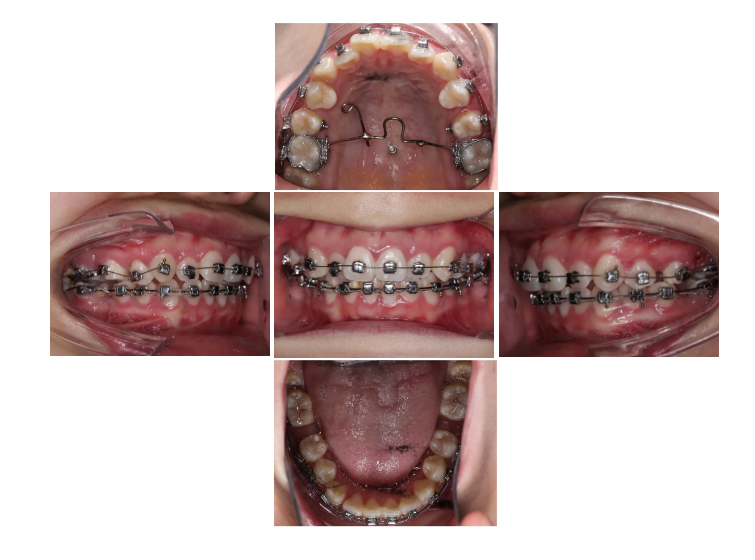

Z2 病例分享 | 一例减数上下颌四颗第一磨牙矫治拥挤病例(雷蕾)